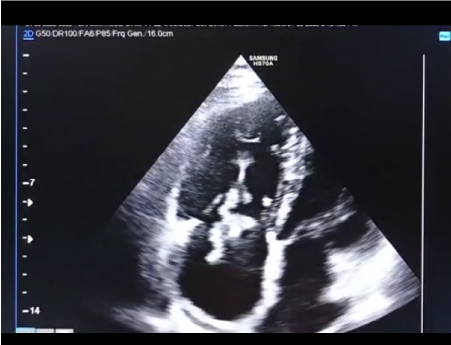

Pacemaker implantation has a very fascinating history. Since the first implantation of human pacemaker technological advancement has helped tremendously in the evolution of different types of pacemaker. Dedicated work by different scientist at different times has enriched the knowledge of several aspects of implantation gradually. Over the time the technology has been modernized to adapt the need of pacing in different clinical situations. However one thing remained constatnt throughout this long history of pacing technique and that is chances of infection and its complications. Infection of the pacemaker lead itself is not uncommon in medical literature. Formation of vegetation, clot, and mass has been reported in pacemaker lead. Here we have reported one such case of pacemaker lead vegetation in a 56-years-old lady. VVIR pacemaker was implanted in this lady 6 years back due to occurrence of syncope in the background of complete heart block. She was doing well until few months back when she had fever. She took medications from nearby healthcare facility but fever persisted. Complete blood count revealed increased TLC with neutrophilic predominance. CRP, ESR was also found to be high. She was started on antibiotics therapy which resulted in defervescence for 2 weeks after which she had fever again. She was advised for CXR and echocardiography. Echocardiogram revealed echogenic structure attached to RV pacing lead and moving along with the lead from RA to RV (Figure 1 and Figure 2). Patient had severe tricuspid regurgitation which is evident in Video 1. Patient was admitted empirical antibiotics therapy started after sample of blood culture was sent. Reports of blood culture including fungal culture were negative. Although percutaneous extraction of pacemaker lead could be done but considering the size, tethered nature of vegetation, fibrosis of the lead due to long history of pacemaker she was transferred to department of Cardiothoracic surgery for extraction of lead. Figure 1 and Figure 2 depicting the pacemaker lead vegetation which is visible from RA to RV attached with the RV lead and moving along with it. Tricuspid valve leaflet was free from any attachment to vegetation. Video 1 showing the vegetation mass along with severe tricuspid regurgitation and dilate RA.

Figure 1: Depicting the pacemaker lead vegetation which is visible from RA to RV attached with the RV lead.

Figure 2: Showing the vegetation attached to RV lead and septal leaflet is free along with dilated RA.